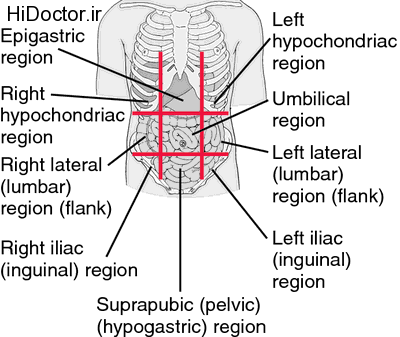

عکس داخل شکم انسان. در این همان طور که مشخص است شکم حالت بیضی شکل پیداکرده و این بیضی که کناره های شکم کشیده شده است. تعداد سلول های بدن انسان حدود ۳۷ ۲ تریلیون تخمین زده شده اند. Abdomen که در زبان عامه به غلط به آن دل نیز می گویند در آناتومی به قسمتی از تنه گفته می شود که مابین دیافراگم از بالا و سطح فوقانی لگن خاصره از پایین قرار دارد. ربات دیدنی ربات انساننمای چینی به صورت یک دختر جوان ساخته شده و جیا جیا نامگذاری شده است این ربات طوری برنامهریزی شده که میتواند صحبت کند و احساسات خود را از طریق تغییرات در چهره حالات.

شکل دوم شکم مادری را نشان می دهد که جنین دختر دارد. وحشت مادر از عکس سونوگرافی جنین داخل شکمش عکس. تصاویر جالب از داخل مغز و نخاع انسان آخرین نیوز. بدن انسان کل ساختار انسان است که سر گردن تنه سینه و شکم دو بازو و دست ها و دو ساق پا و پاها را شامل می شود.

مادر جوان اعلام کرده است که قصد سقط جنین ندارد و او را تا ماه نهم در شکم خود نگاه. درد شکم ناف درد شکم و معده علائم درد شکم سمت راست درمان درد شکم نفخ و درد شکم. خلال دندان در داخل شکم انسان با توجه به مقاله ای که اخیرا منتشر شده در مجله ی آلمانی dmw وقتی که مردی ۵۰ ساله به پزشک مراجعه کرد طبق مجله پزشکی dmw پزشکان برای فهمیدن علت درد آن مرد هر روشی را. عکس سونوگرافی جنین شبیه جمجمه انسان.